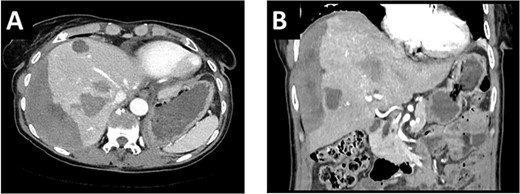

After multidisciplinary tumor board (MDT) discussion, neoadjuvant chemotherapy with six cycles of FOLFOXIRI and Bevacizumab followed by liver-first approach was decided. Restaging after 3 months showed stable disease of the CRLM, therefore, chemotherapy was continued. After 12 cycles, restaging revealed a size reduction of 12% of the CRLM (Fig. 1B). CEA decreased from 69 to 6.1 ug/l. The patient was then admitted to our department for the evaluation of a curative intent CRLM resection. The radiological work-up revealed three remaining metastases on the left- and seven on the right hemiliver. Volumetry illustrated a standardized FLR (sFLR) for a right hemihepatectomy of 30%. In an MDT and the patient was deemed amenable to ALPPS surgery due to the marginal sFLR, bilobar metastases and exceptionally good performance status. Preoperative liver function tests showed normal liver function (LiMAx 450 mcg/kg/h, cut-off >315 mcg/kg/h and ICG R15: 4.0%, cutoff <12%). Although liver biopsy is not routinely performed before ALPPS, MDT recommended a biopsy of the healthy liver to rule out chemotherapy-associated steatohepatitis after 12 cycles of FOLFOXIRI and Bevacizumab in order to ensure a safe liver resection. The biopsy showed signs of subacute hepatocyte demise without fibrosis or cirrhosis. The day after the liver biopsy, the patient collapsed and was admitted to the emergency department of another hospital. CT scan showed a large intrahepatic hematoma (Fig. 2) without active bleeding probably secondary to the biopsy procedure. Due to a hemoglobin drop of 12 g/l a day later and the enlargement of the hematoma in follow-up CT scan, the patient was admitted to angiography, which showed several subcapsular liver bleedings, therefore the right hepatic artery was embolized. Luckily, an accessory right hepatic artery arising from the superior mesenteric artery was present. This enabled us to stay on track with the ALPPS procedure as the right hemiliver would be otherwise without any blood supply (Fig. 3). In synopsis of those findings, the operation was scheduled.

CT-angiography showing the accessory right hepatic artery originating from the superior mesenteric artery.